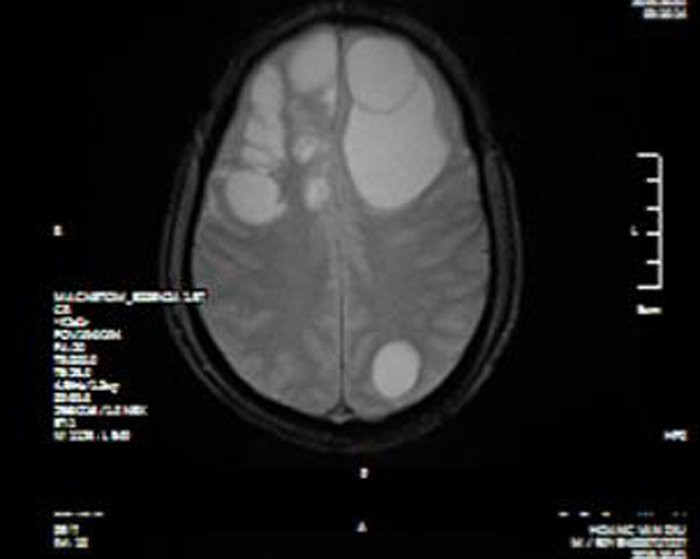

Hình ảnh phim chụp CT sọ não bệnh nhân có sán làm tổ trong não gây suy giảm trí nhớ.

Tại bệnh viện, kết quả chụp CT sọ não bệnh nhân cho thấy có ổ sán khổng lồ ở cả hai bán cầu trái gây phù não diện rộng. Bệnh nhân được chỉ định can thiệp ngoại khoa bằng phương pháp phẫu thuật.